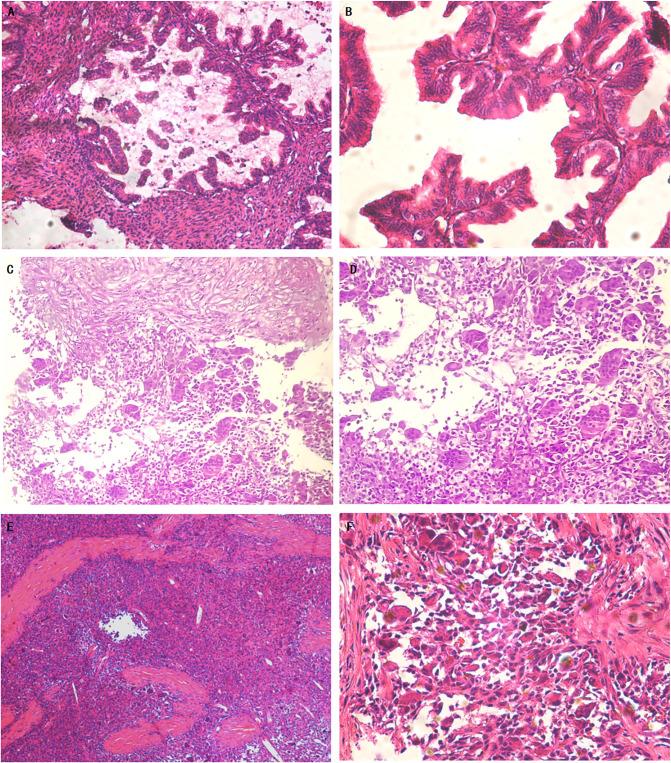

Ovarian mucinous tumors with sarcomatous mural nodules are rare. Sarcomatous nodules have a bad prognosis. Its diagnosis and treatment are controversial.It is still controversial whether malignant mural nodules represent a dedifferentiated form of mucinous tumors or collisional tumors. This is a case report of a 32-year-old female diagnosed with ovarian mucinous tumor recurred as a mucinous carcinoma combined with sarcomatoid and undifferentiated sarcoma mural nodules after surgery and chemotherapy. The primary lesion did not have a sarcomatous component after comprehensive sampling and repeated review, while the recurrent lesion had a predominantly sarcomatous component. The patient received a second operation and postoperative chemotherapy plus Anlotinib with no progression at 16 months of follow-up. Primary mucinous carcinoma and sarcomatous mural nodules revealed the same K-RAS mutation(c.35G>T, pG12V), TP53 mutation (c.817C>T, p.R273C), MLL2 mutation(c.13450C>T, p.R4484) and NF1 mutation(c.7876A>G, p.S2626G). We present a comprehensive analysis on morphologic characteristics, molecular detection results, clinical management, and prognosis of ovarian mucinous tumors with mural nodules of sarcomatoid and undifferentiated sarcoma. Mutation sharing between primary mucinous carcinoma and recurrent sarcomatous nodules supports monoclonal origin of primary and recurrent tumors, suggesting a tendency for sarcomatous differentiation during the progression of epithelial tumors. Malignant mural nodules represent dedifferentiation in mucinous ovarian tumors rather than collision of two different tumor types. Therefore, it is imperative to conduct comprehensive sampling, rigorous clinical examination, and postoperative follow-up in order to thoroughly evaluate all mural nodules of ovarian mucinous tumors due to their potential for malignancy and sarcomatous differentiation.

伴有肉瘤样壁结节的卵巢黏液性肿瘤较为罕见。肉瘤样结节预后不良。其诊断和治疗存在争议。恶性壁结节是黏液性肿瘤的去分化形式还是碰撞性肿瘤仍存在争议。本文报告一例32岁女性,诊断为卵巢黏液性肿瘤,术后化疗后复发为黏液腺癌合并肉瘤样和未分化肉瘤壁结节。经全面取材及反复阅片,原发灶无肉瘤成分,而复发病灶以肉瘤成分为主。患者接受了二次手术及术后化疗加安罗替尼治疗,随访16个月无进展。原发黏液腺癌和肉瘤样壁结节显示相同的K-RAS突变(c.35G>T,p.G12V)、TP53突变(c.817C>T,p.R273C)、MLL2突变(c.13450C>T,p.R4484)和NF1突变(c.7876A>G,p.S2626G)。我们对伴有肉瘤样和未分化肉瘤壁结节的卵巢黏液性肿瘤的形态学特征、分子检测结果、临床处理及预后进行了综合分析。原发黏液腺癌与复发肉瘤样结节间的突变共享支持原发和复发肿瘤的单克隆起源,提示上皮性肿瘤进展过程中存在肉瘤样分化倾向。恶性壁结节代表黏液性卵巢肿瘤的去分化而非两种不同肿瘤类型的碰撞。因此,鉴于卵巢黏液性肿瘤壁结节有恶变及肉瘤样分化的可能,必须进行全面取材、严格的临床检查及术后随访,以彻底评估所有壁结节。